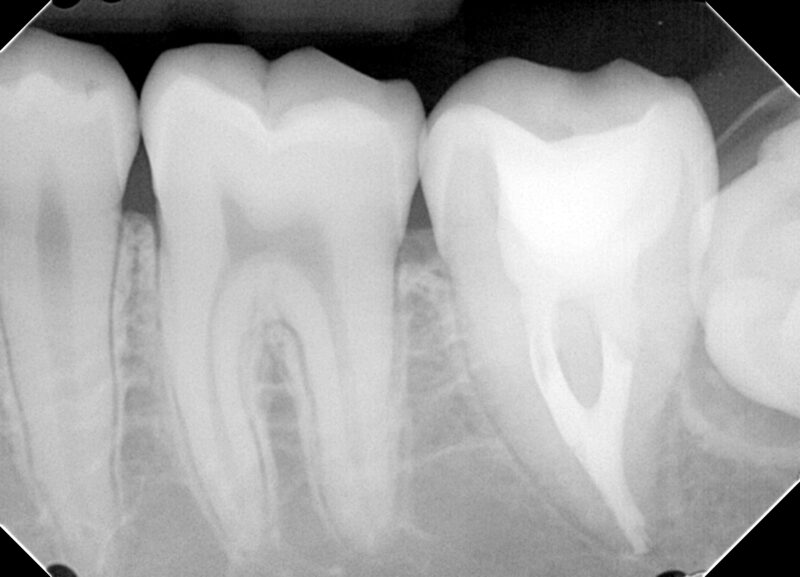

【術前レントゲン】

歯冠は大きく崩壊しており、歯髄に達する大きなう蝕が認められます。また、若干根尖部に骨欠損が認められます。

【術直後のレントゲンと口腔内写真】

根の管はY字状になっており、緊密に根管充填がなされていることが分かります。

【経過観察時(術後3か月後)レントゲン】

根の先の骨が回復していることが分かります。